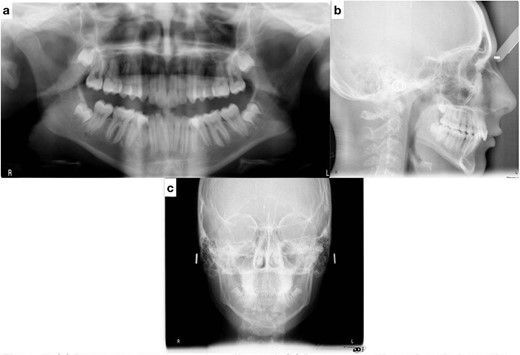

Post-treatment clinical examination showed that crowding was relieved by a 4-mm increase in the intermolar width of the maxillary and mandibular arches. In addition, a class I molar and canine relationship was achieved with good occlusion (Fig. 5) and a pleasing smile (Fig. 6). Post-treatment lateral cephalometric radiographs showed that the mandible had grown forward in the sagittal dimension, improving the skeletal profile (Fig. 7b). The upper incisors were proclined by 15° to achieve ideal labio-lingual inclination for optimum aesthetics; the lower incisor was optimally positioned to achieve ideal overjet and overbite (Fig. 7b). Mandibular anterior teeth were intruded to correct the impinging overbite and level the Curve of Spee. Finally, the patient was referred to an oral surgeon for extraction of the third molars.

(a) Post-treatment panoramic radiograph; (b) post-treatment lateral cephalometric radiograph